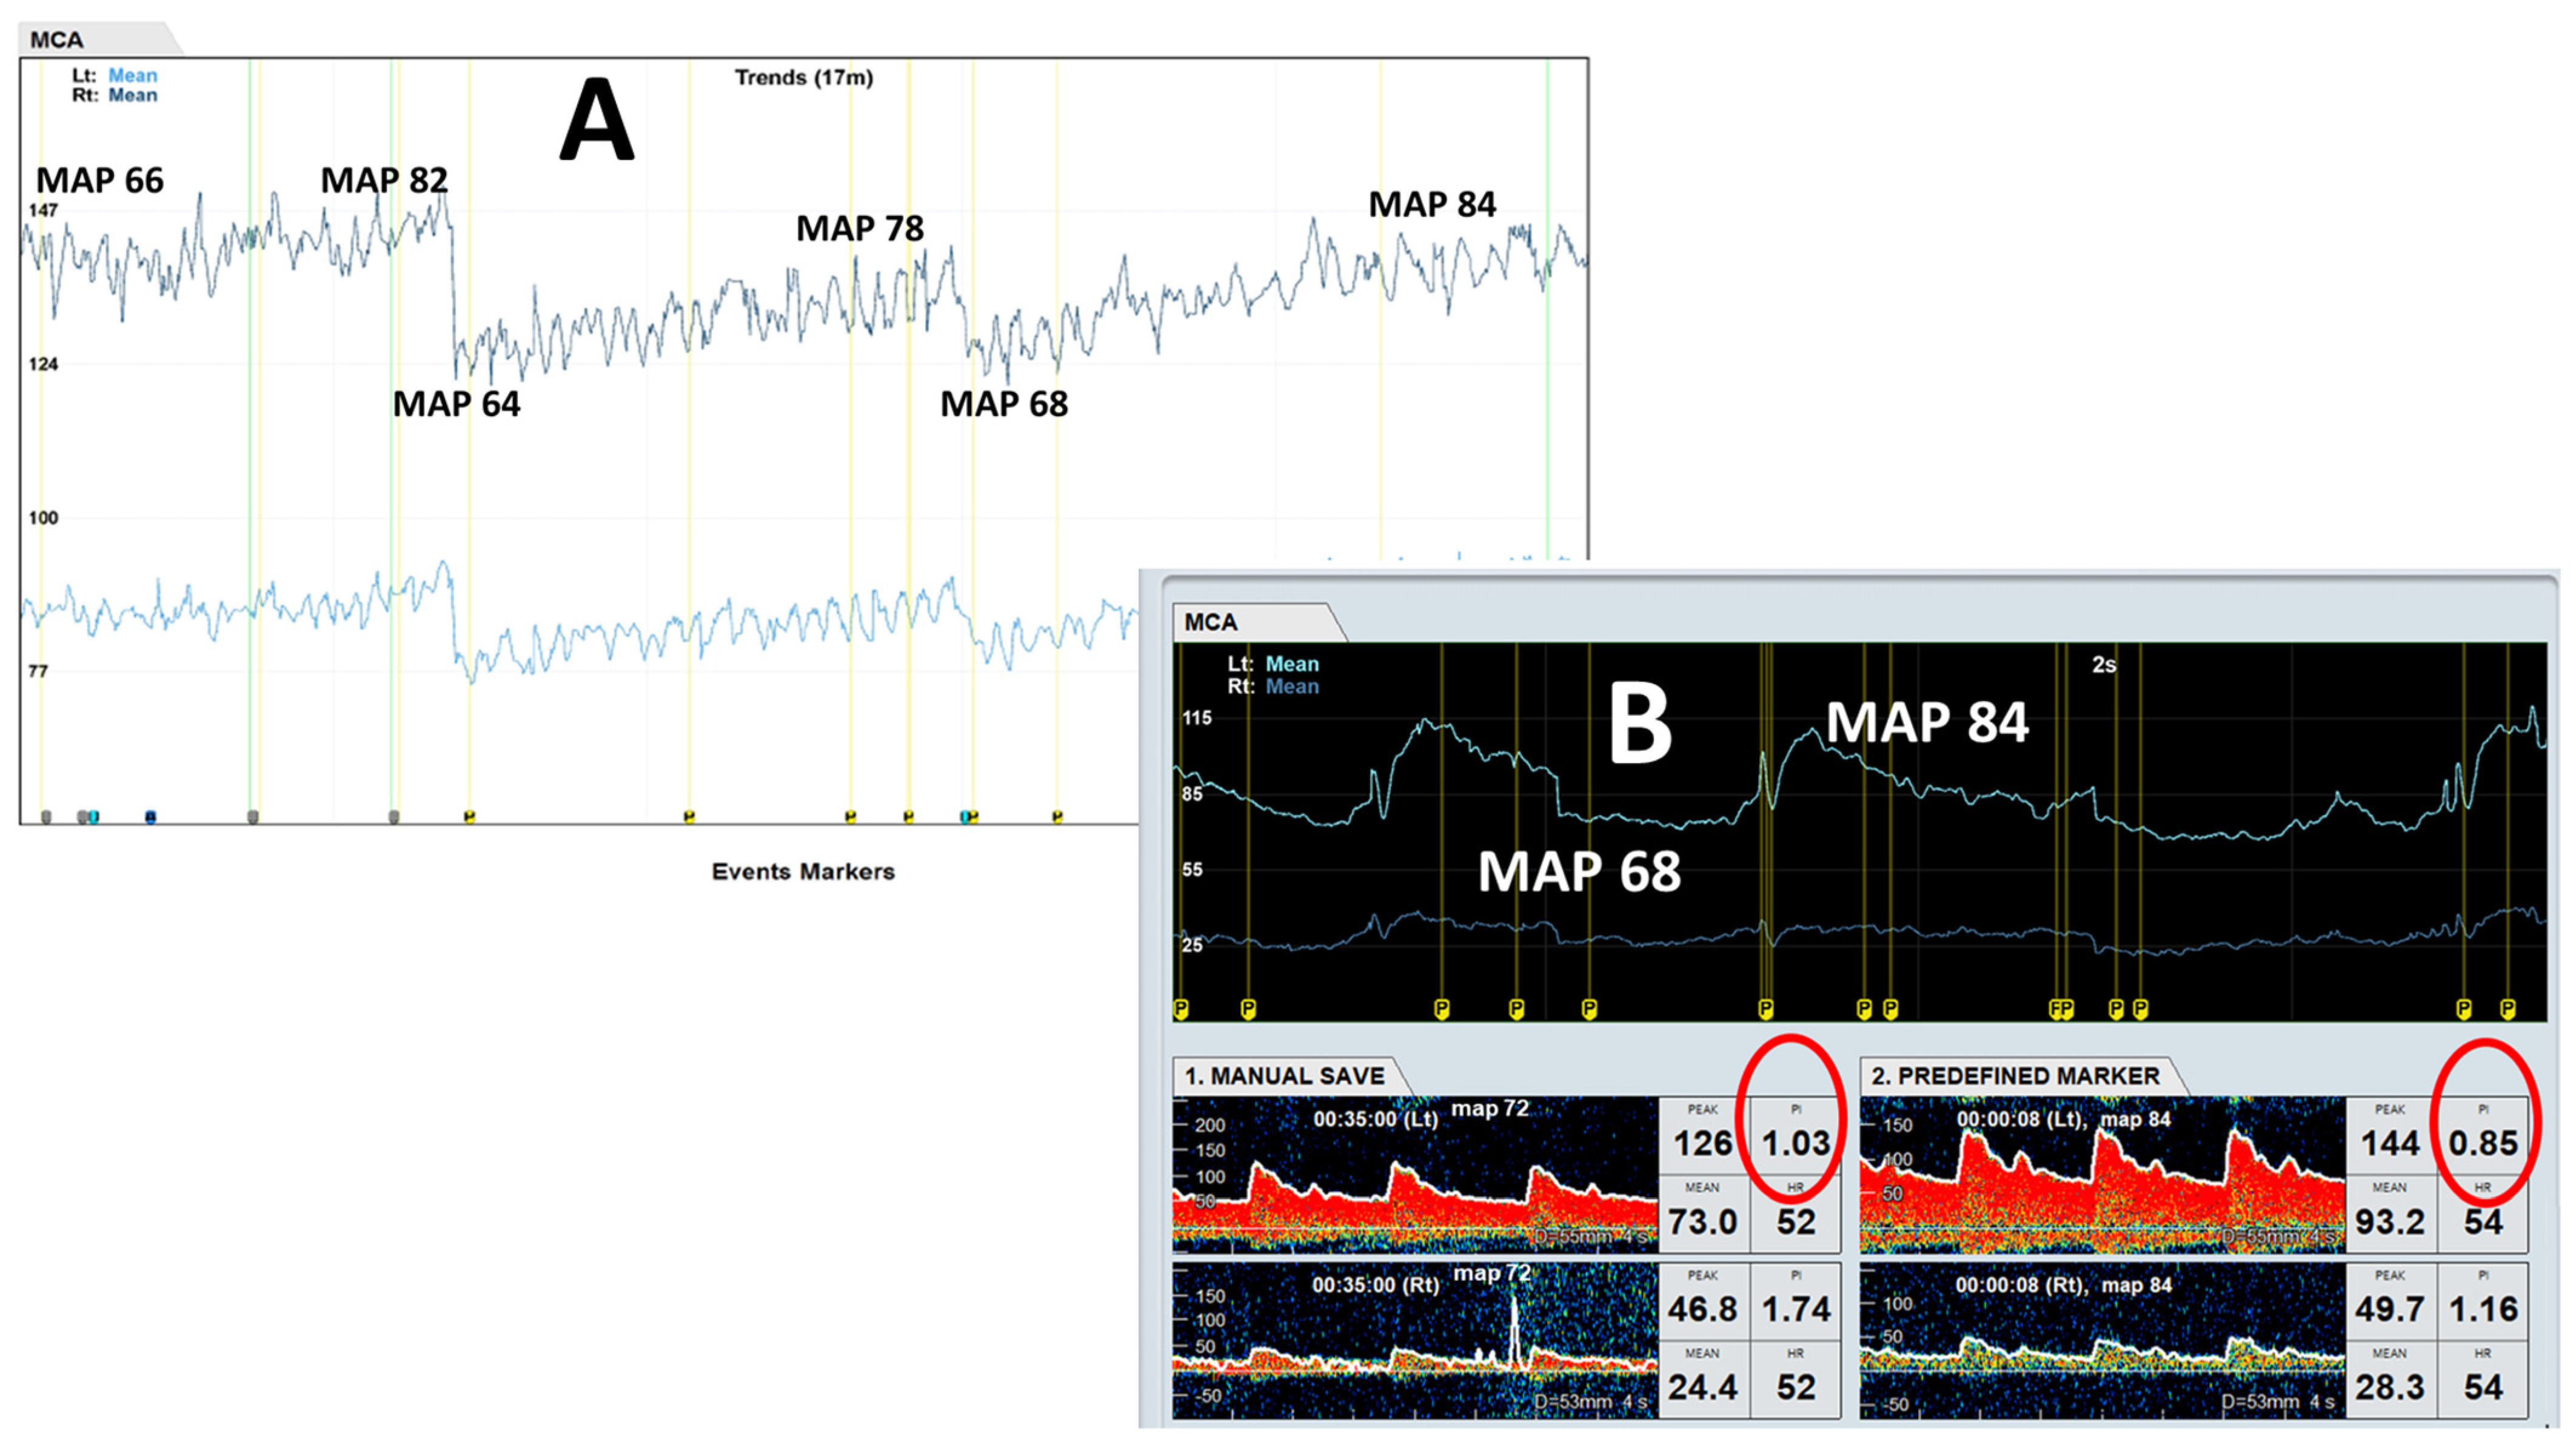

3.1. Patient A